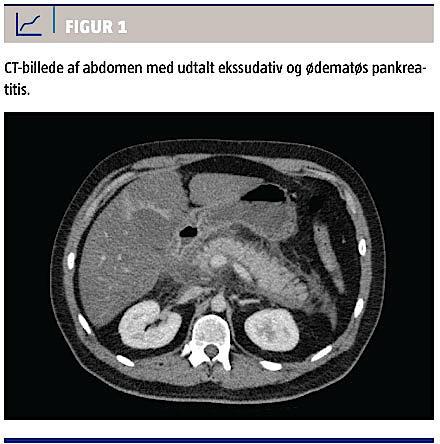

Umiddelbart blev patienten vurderet til at have en mild pankreatitis (modificeret Glasgow score = 1). Behandling med smertestillende midler, væsketerapi og i.v. indgift af insulin blev påbegyndt. Ultra-lydskanning af pancreas vanskeliggjordes af hans adipositas, men der var ingen tegn på galdesten eller galdestase. Leveren var forstørret og steatotisk. CT af abdomen (Figur 1) viste udtalt interstitiel, ødematøs pankreatitis og udtalt duodenitis. Pga. den svære pankreatitis blev han overflyttet til en intensivafdeling, hvor der udvikledes en deliriøs tilstand, hvorefter han blev sederet og intuberet. Tilstanden blev hurtigt forværret med udvikling af feber samt cirkulatorisk og renalt svigt. Idet han havde sepsis, metabolisk acidose og multiorgansvigt, blev han overflyttet til et universitetshospital. Han afgik ved døden to døgn efter den første kontakt på skadestuen.